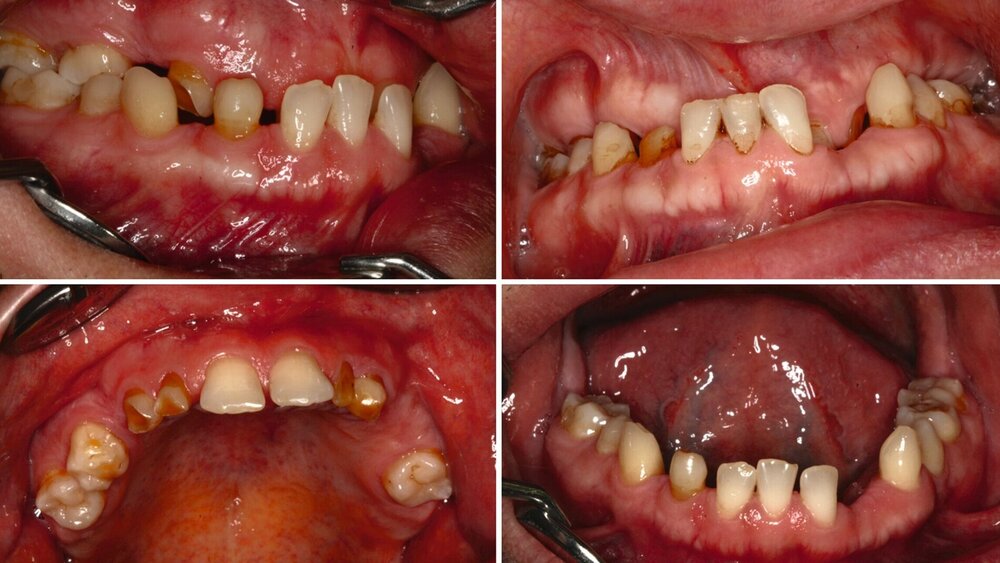

Ein 30-jähriger Patient stellte sich mit multipler Oligodontie (15 fehlende bleibende Zähne), Persistenz von Milchzähnen sowie ausgeprägter Dysgnathie mit progenem Deckbiss vor. Klinisch zeigten sich hypoplastische Restzähne, Fehlstellungen und erhebliche funktionelle Beeinträchtigungen (Abbildung 1). Sein Wunsch bestand in einer möglichst optimalen ästhetischen und funktionellen Versorgung seiner für ihn äußerst unbefriedigenden Gebisssituation. Die molekulargenetische Analyse bestätigte eine homozygote Mutation im WNT10A-Gen als Ursache der Zahnagenesie.

Zu Beginn der Behandlungsplanung wurden ein digitales OPG sowie Planungsmodelle erstellt (Abbildung 2). Interdisziplinär wurden mit dem Prothetiker, Chirurgen und Zahntechniker anhand der vorliegenden Modellanalysen und der klinischen Situation des Patienten verschiedene Therapieoptionen entwickelt und gemeinsam bewertet.